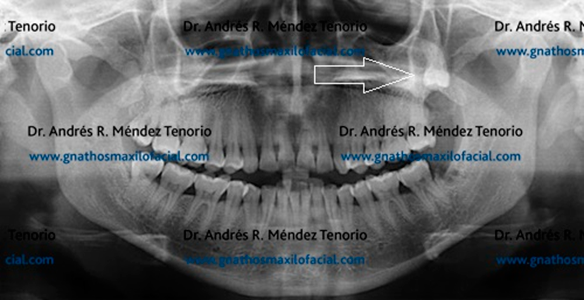

| Tras la extracción de estas piezas dentales y la rehabilitación dental, la higiene y la comodidad del paciente se incrementan con una dentición hasta el 2º molar en los cuatro cuadrantes de los maxilares |